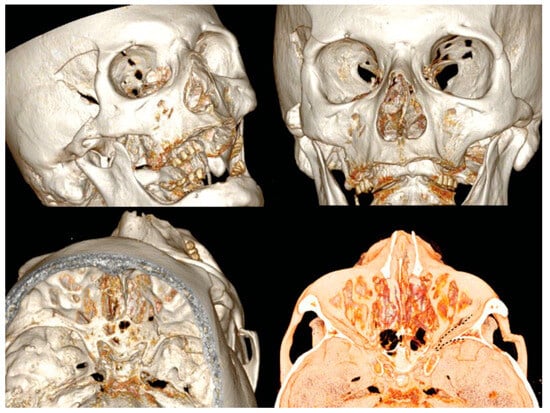

A new spiral craniomaxillofacial CT scan with coronal, sagittal, and three-dimensional (3D) reconstruction was performed the following morning. The imaging examination revealed a displacement of the lateral wall of the right SOF which was reduced in amplitude. The fracture was classified as a rare frontosphenotemporal fracture, according to Pellerin et al. [8], that is frequently associated with visual impairment (Figure 2). This pattern of fracture is characterized by the preservation of integrity of the lateral orbital wall and its whole dislocation. A thin layer of epidural blood of approximately 7 mm at the middle temporal fossa was also noticed, adjacent to the greater wing of the sphenoid bone.

Figure 2. 3D CT scan reconstruction showing four different projections of frontosphenotemporal Pellerin et al fracture pattern; note in frontal view (up right), SOF size reduction caused by medial displacement of the entire right lateral orbital wall; the black dashed line in the intracranial view (down right) shows the medial collapse of lateral orbital wall into the SOF. CT, computed tomography; SOF, superior orbital fissure; 3D, three-dimensional.